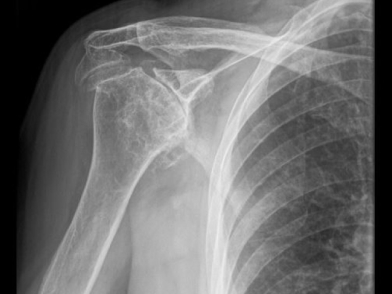

Οι απεικονιστικές εξετάσεις στην αρθρίτιδα του ώμου περιλαμβάνουν κατ’ αρχάς, μία πλήρη σειρά κοινών ακτινογραφιών, η οποία είναι συνήθως αρκετή ώστε να αναδείξει τη φθορά των αρθρικών επιφανειών αλλά και επιπρόσθετες οστικές αλλοιώσεις. Επιπλέον των ακτινογραφιών, μπορούν να χρησιμοποιηθούν τόσο η αξονική όσο και η μαγνητική τομογραφία , οι οποίες με τη σειρά τους βοηθούν στην προεγχειρητική αξιολόγηση της μορφολογίας της ωμογλήνης καθώς και της κατάστασης των μυών και των τενόντων του στροφικού πετάλου αντίστοιχα.

Η αρθρίτιδα του ώμου μπορεί να διακριθεί ως πρωτοπαθής, δηλαδή άγνωστης αιτιολογίας, ή ως δευτεροπαθής, λόγω διαφόρων παθολογικών καταστάσεων, όπως είναι η μετατραυματική, η μετά από εξάρθρημα, η φλεγμονώδης και κρυσταλλική αρθροπάθεια, η οστεονέκρωση, η νευροπαθητική αρθρίτιδα (αρθροπάθεια Charcot) και η αρθροπάθεια του στροφικού πετάλου.

Πιο συγκεκριμένα, η μετατραυματική αρθρίτιδα συνήθως προκύπτει ως αποτέλεσμα ατελειών στην αρθρική επιφάνεια που δημιουργούνται μετά από ένα κάταγμα, ενώ η αρθροπάθεια μετά από εξάρθρημα προκύπτει από τις κακώσεις που υφίσταται ο αρθρικός χόνδρος ακόμα και μετά από ένα μεμονωμένο επεισόδιο εξαρθρήματος. Η αρθροπάθεια του στροφικού πετάλου αποδίδεται στην προοδευτική ανεπάρκεια του στροφικού πετάλου λόγω της παρουσίας μεγάλων ή μαζικών ρήξεων οι οποίες οδηγούν στην εγγύς (προς τα άνω) μετανάστευση της βραχιονίου κεφαλής, οπότε και προσκρούει στο ακρώμιο, οδηγώντας κατ’ αυτόν τον τρόπο σε φθορά του αρθρικού χόνδρου. Η οστεονέκρωση είναι το αποτέλεσμα της διακοπής της αιματικής ροής στη βραχιόνιο κεφαλή λόγω ενός αριθμού γνωστών τραυματικών (κατάγματα, εξαρθρήματα κλπ.) αλλά και μη τραυματικών (συστηματική λήψη κορτικοστεροειδών, αλκοολισμός, παθήσεις του οστικού μυελού κλπ.), οδηγώντας κατ’ αυτόν τον τρόπο σε κυτταρικό θάνατο, καθίζηση του υποχονδρίου οστού και εντέλει, βλάβη και εκφύλιση του αρθρικού χόνδρου. Τέλος, στις φλεγμονώδεις και τις κρυσταλλικές αρθροπάθειες η αιτία της εκφύλισης της άρθρωσης και της προοδευτικής αρθρίτιδας είναι είτε μια συστηματική αυτοάνοση νόσος (π.χ. η ρευματοειδής αρθρίτιδα), είτε η εναπόθεση κρυστάλλων ουρικού ή άλλων αλάτων στις αρθρικές επιφάνειες.